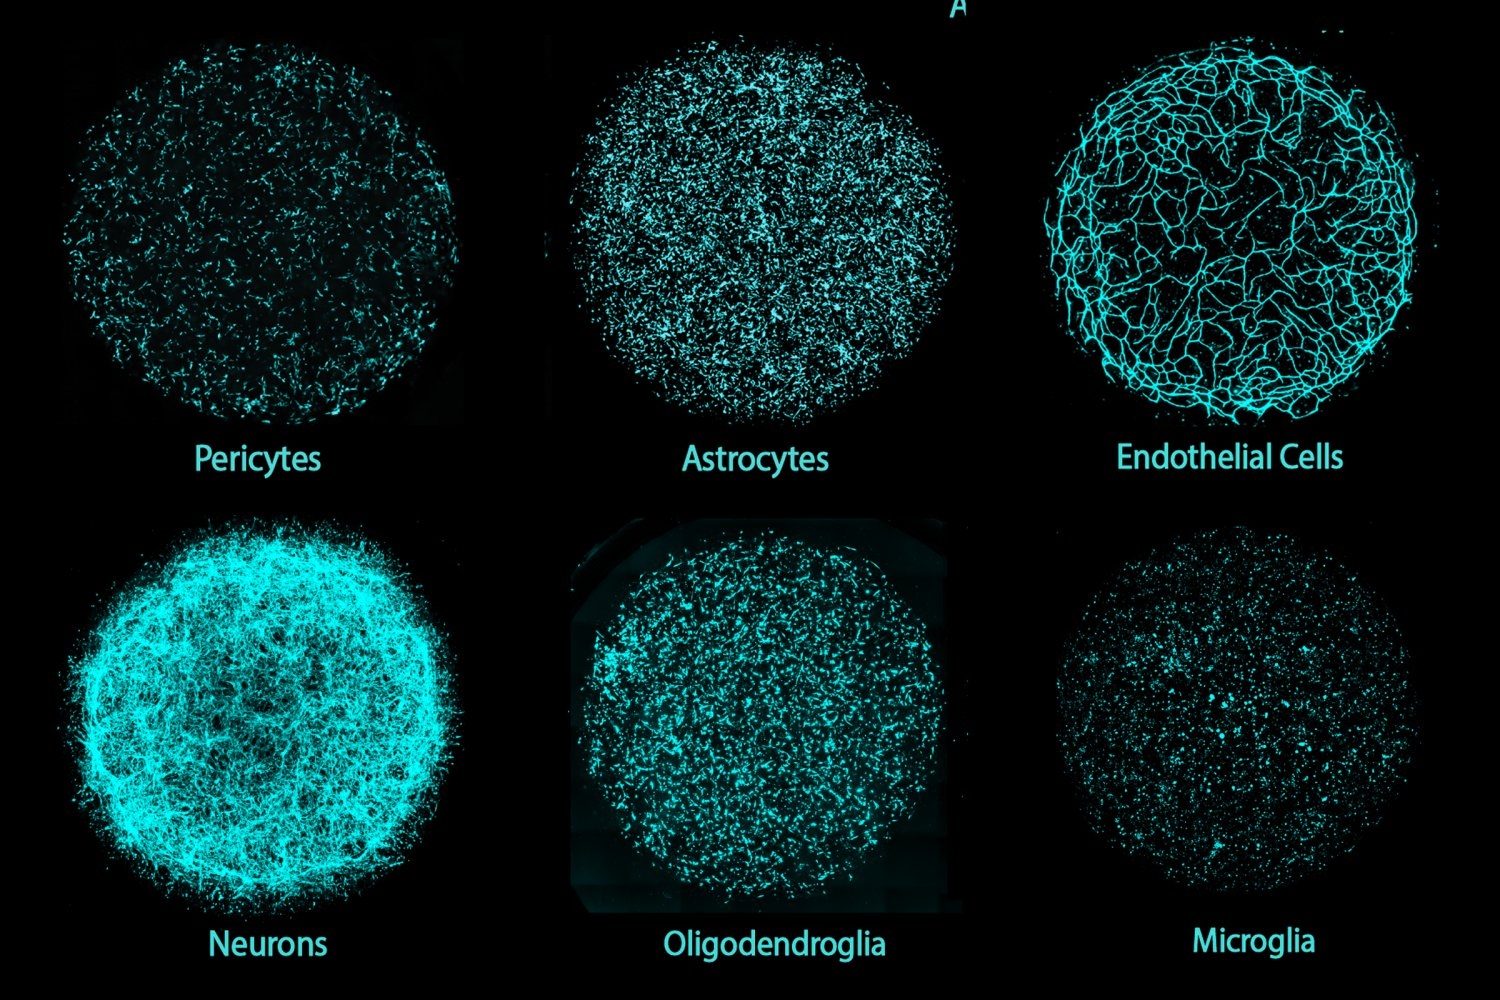

- MIT researchers invent new human brain model to enable disease research, drug discoveryCultured from induced pluripotent stem cells, “miBrains” integrate all major brain cell types and model brain structures, cellular interactions, activity, and pathological features.